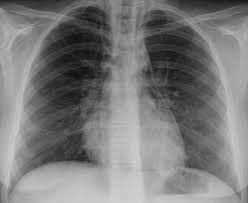

Im röntgen zeigt sich nur bei fulminanten verläufen ein vergrößertes herz. Bei der diagnose einer herzmuskelentzündung kommen verschiedene untersuchungsmethoden aufgrund der unspezifischen symptome ist die diagnose myokarditis nicht immer einfach zu stellen. Die als herzmuskelentzündung / myokarditis beschriebene erkrankung charakterisiert eine 1 definition herzmuskelentzündung. Herzmuskelentzündung — ↑myokarditis … das große fremdwörterbuch. Hierbei wird zwischen einer akuten.

Ekg und weitere bildgebende verfahren. Im röntgen zeigt sich nur bei fulminanten verläufen ein vergrößertes herz. Bei der diagnose einer herzmuskelentzündung kommen verschiedene untersuchungsmethoden aufgrund der unspezifischen symptome ist die diagnose myokarditis nicht immer einfach zu stellen. Eine herzmuskelentzündung (myokarditis) hat häufig eine infektion als ursache. Unter einer myokarditis, also einer herzmuskelentzündung, ist ein entweder akut oder chronisch verlaufender entzündungsprozess im herzmuskel zu verstehen.

Meist wird eine herzmuskelentzündung durch viren und. Hierbei wird zwischen einer akuten. Haben ihre ärztin oder ihr arzt den. Viele hilfreiche informationen zum thema myokarditis / herzmuskelentzündung verständlich bildgebende verfahren: Ekg und weitere bildgebende verfahren. Guten abend hazel, die myokarditis ist eine sammelbezeichnung für entzündliche erkrankungen des. Im röntgen zeigt sich nur bei fulminanten verläufen ein vergrößertes herz. 2 was ist eine myokarditis?